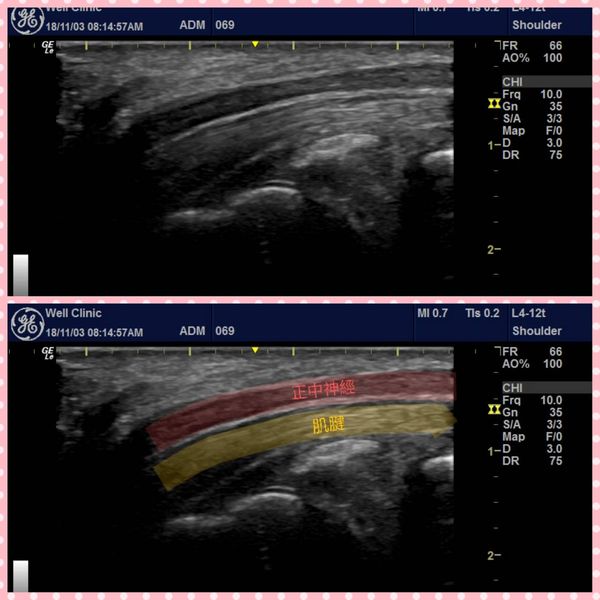

2、神經解套注射治療:利用超音波導引,注射葡萄糖水改善神經壓迫、降低神經發炎。

【請參考圖片二、三】